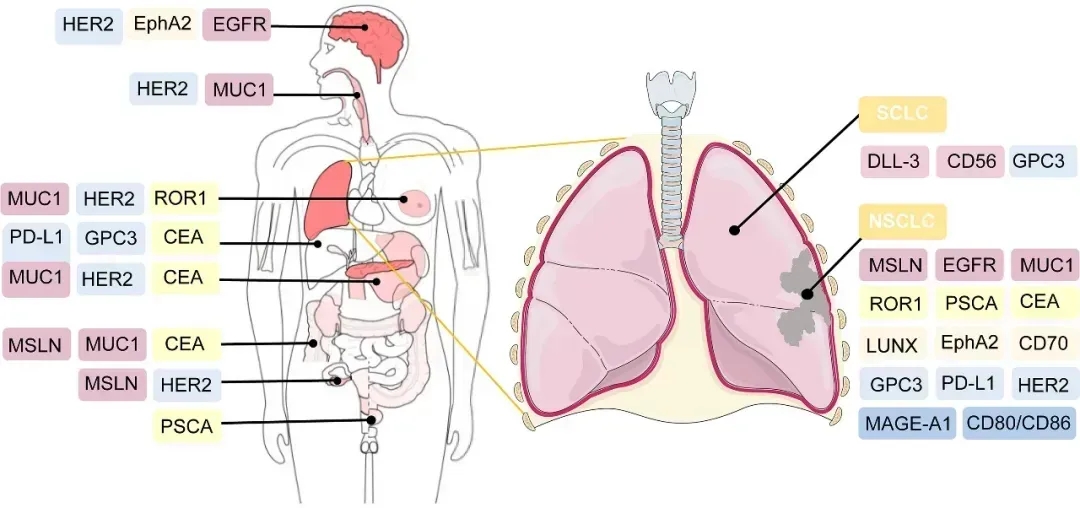

· CAR-T疗法的在招靶点及癌种 ·

好消息是,目前有多款CAR-T临床实验正在火热招募中,主要针对Claudin18.2、GPC3、GUCY2C、PSMA、CEA、间皮素(mesothelin)、MUC-1、BCMA、CD1、CD20等靶点。以及胰腺癌、胃癌、肝癌、结直肠癌、神经胶质瘤、肺癌、多发性骨髓瘤、多发性骨髓瘤、弥漫大B细胞淋巴瘤等癌种。

▼CAR-T细胞疗法的潜在治疗靶点

做过基因检测的患者,可自行查看基因检测报告,一旦发现存在上述突变,可将近期病理报告、基因检测报告等资料汇总后,提交至医学部,初步评估是否有机会参加相关临床试验。一旦审核通过,有机会获得”天价“疗法免费治疗的机会。